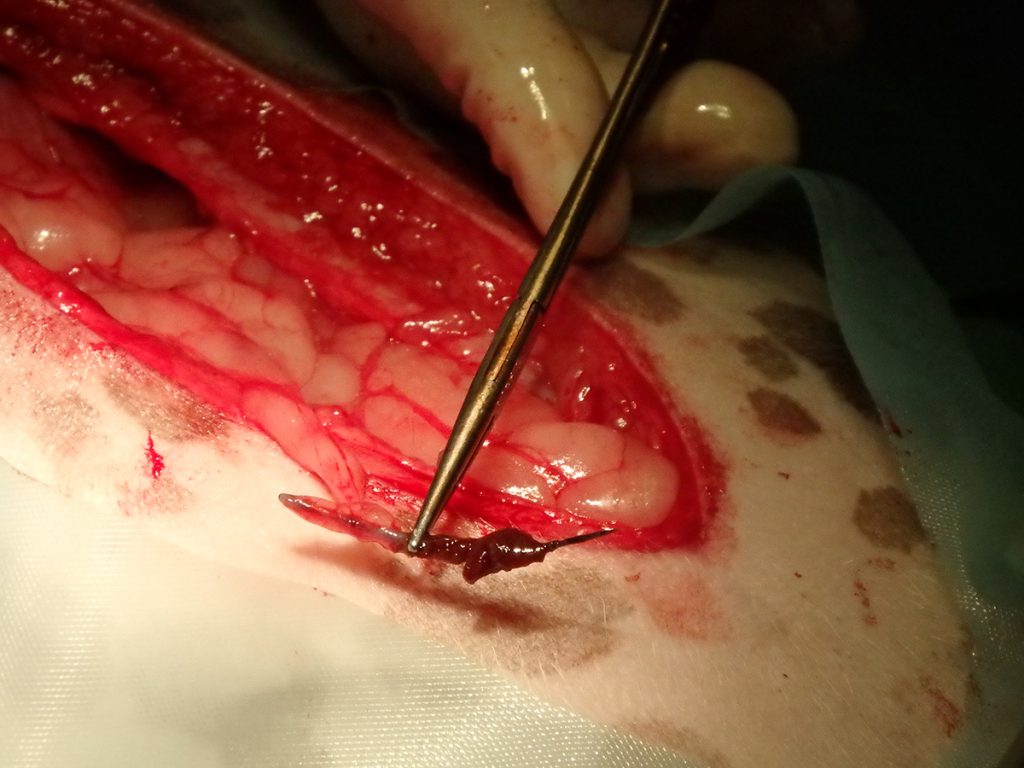

Na het openen van de buik en het verwijderen van wat vet, is de chirurg gaan zoeken. Al snel vindt hij aan de voorzijde van de maag een vreemd vliesje. Dit blijkt een stukje vet en vlies te zijn, wat op het oogje van de naald verkleefd zat. Ruim 2/3 van de naald blijkt in een leverlob te zitten. De naald blijkt er niet eenvoudig uitgetrokken te kunnen worden. Hij zit aardig vast. Dit suggereert dat hij er misschien al iets langer zit. Bij het verwijderen van de naald ontstaat er een klein scheurtje in de lever. De bloeding kan worden gestelpt met een speciaal matje dat stolling bevordert. Hierna is het een kwestie van de buik sluiten en Lady mag weer wakker worden.